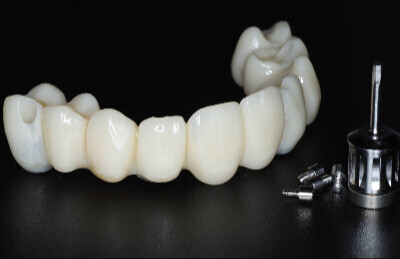

Navigovaná chirurgia, 5 implantátov

Autor práce Dr. Michal Repaši

Zubný technik Vasil Csopej

22. september 2021